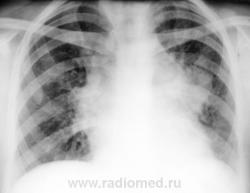

Пол пациента: Женский пол Тип патологии: Воспалительное заболевание неинфекционной природы Область исследования: Грудная клетка и верхние дыхательные пути Методы исследования: Rg Болеет около 3-х недель. Жалобы на одышку , сердцебиение. 10 дней принимала антибиотики. Возможно это сердечная патология? Бокового снимка нет. https://radiomed.ru/sites/default/files/styles/case_slider_image/public/user/12/1.Bod_..jpg?itok=E-KH1jBz https://radiomed.ru/sites/default/files/styles/case_slider_image/public/user/12/2.Bod_.jpg?itok=rzvtyFWz https://radiomed.ru/sites/default/files/styles/case_slider_image/public/user/12/3.Bod_..jpg?itok=2JC7feyE ID:1839 Втр, 16/03/2010 - 16:36 #1 tatyana Не на сайте Был на сайте: 4 года 1 месяц назад Зарегистрирован: 24.06.2009 - 08:33 Публикации: 2090 bogdan wrote: Возможно это сердечная патология? Вряд ли, скорее опухолевая "самоуверенность дилетантов - предмет зависти профессионалов" Втр, 16/03/2010 - 18:29 #2 ElenaG Не на сайте Был на сайте: 15 лет 7 месяцев назад Зарегистрирован: 23.02.2010 - 23:21 Публикации: 69 Хотелось бы узнать возраст пациентки.ятоже за онкологию,Хотя и правый корень кажется расширен.Не окажется ли это лимфоузлами? Втр, 16/03/2010 - 18:30 #3 Лукаш Не на сайте Был на сайте: 10 лет 3 месяцев назад Зарегистрирован: 05.03.2010 - 13:28 Публикации: 47 А может быть и саркоидоз или ЛГМ (возраст какой?). Есть признаки сдавления верхней полой вены? Ой, больной, что-то мне ваш снимок не нравится. Но ничего - щас мы в Фотошопе все подправим. Втр, 16/03/2010 - 20:19 #4 bogdan Не на сайте Был на сайте: 7 лет 1 месяц назад Зарегистрирован: 07.01.2010 - 16:14 Публикации: 45 Девушке 23 года Втр, 16/03/2010 - 21:04 #5 Петрович Не на сайте Был на сайте: 7 лет 2 месяцев назад Зарегистрирован: 22.03.2009 - 01:13 Публикации: 3908 А почему не сделана хотя бы левая боковая проекция? Болеет давно, клиника серьёзная. Пора уже и томограммы делать. Вон как средостение расширено. Неоднозначно всё Втр, 16/03/2010 - 23:53 #6 Лукаш Не на сайте Был на сайте: 10 лет 3 месяцев назад Зарегистрирован: 05.03.2010 - 13:28 Публикации: 47 Возраст молодой - надо исключать лимфогранулематоз: поискать периферические лимфоузлы, при нахождении - пропунктировать. Еще УЗИ ОБП - на предмет парааортальных л/у. Ой, больной, что-то мне ваш снимок не нравится. Но ничего - щас мы в Фотошопе все подправим.

Хотелось бы узнать возраст пациентки.ятоже за онкологию,Хотя и правый корень кажется расширен.Не окажется ли это лимфоузлами?

А почему не сделана хотя бы левая боковая проекция? Болеет давно, клиника серьёзная. Пора уже и томограммы делать. Вон как средостение расширено.

Неоднозначно всё